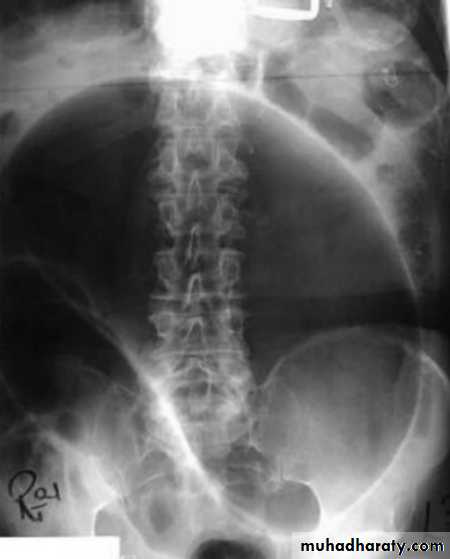

Sigmoid volvulus

Inverted U-shaped appearance of distended sigmoid loopLargest and most dilated loops of bowel are seen with volvulus

Loss of haustra

Coffee-bean sign à midline crease corresponding to mesenteric root in a greatly distended sigmoid

Sigmoid volvulus – bowel loop points to RUQ

Cecal volvulus – bowel loop points to LUQ

Bird’s-beak or bird-of-prey sign à seen on barium enema as it encounters the volvulated loop